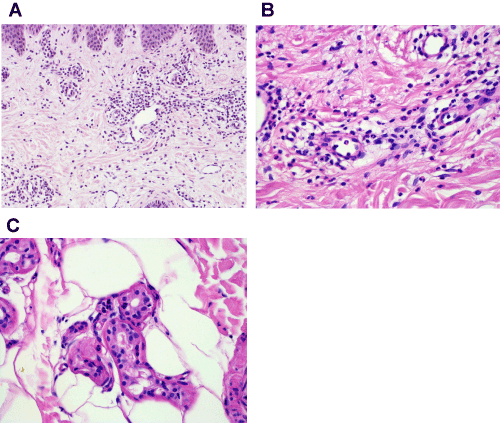

Figure 2a. HE stain. Magnification 20x. Note dense perivascular and interstitial inflammatory infiltrate composed of lymphocytes and neutrophils devoid of epidermal changes or vascular damage.

Intensive investigations performed to rule out differential diagnoses (i.e., the adult form of Morbus Still or systemic vasculitis) did not show any abnormalities: there were no signs of organ involvement; liver enzymes were normal, urine analysis showed no proteinuria, and echocardiography did not reveal any signs of endocarditis, neither did abdominal sonography. Due to the gluteal location of the cutaneous erythema, the patient was examined proctologically and a magnetic resonance image (MRI) of the pelvis and chest was conducted that both showed no signs of vasculitis or hidden inflammatory foci. Hence, a skin biopsy was taken from lesional skin that revealed a regular epidermis, with a dense perivascular and interstitial infiltration of lymphocytes and lots of neutrophils (Figure 2a), but without nuclear debris or nuclear dust and without leukocytoclasia. Signs of vasculitis, e.g. destruction of vascular walls, transmural inflammatory cells or obstruction of blood vessels were not noted. There was no papillary edema and no evidence for bacteria or fungi in gram and PAS staining. Intriguingly, neutrophilic epitheliotropism of eccrine gland epithelium could be found (Figure 2b and c). Thus, erysipelas-like-eruption was diagnosed. The unsatisfying course of disease in our case prompted us to reconsider our diagnosis of erysipelas and intensive anamnesis of the patient revealed additional interesting information: our patient was of Turkish descent, her father was a Turk.

Figure 2b. HE stain. Magnification 40x. Please note the intact vascular wall and missing nuclear dust.

Figure 2c. HE stain. Magnification 40x. Neutrophils within secretory epithelia of sweat glands.